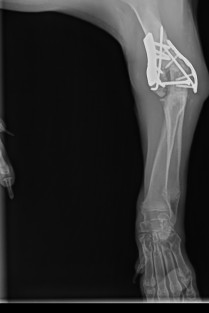

Orthopédie

La première journée sera consacrée à la physiopathologie, l’imagerie et la chirurgie. La seconde journée sera consacrée à la physiothérapie et à la rééducation fonctionnelle, avec de nombreux travaux pratiques.